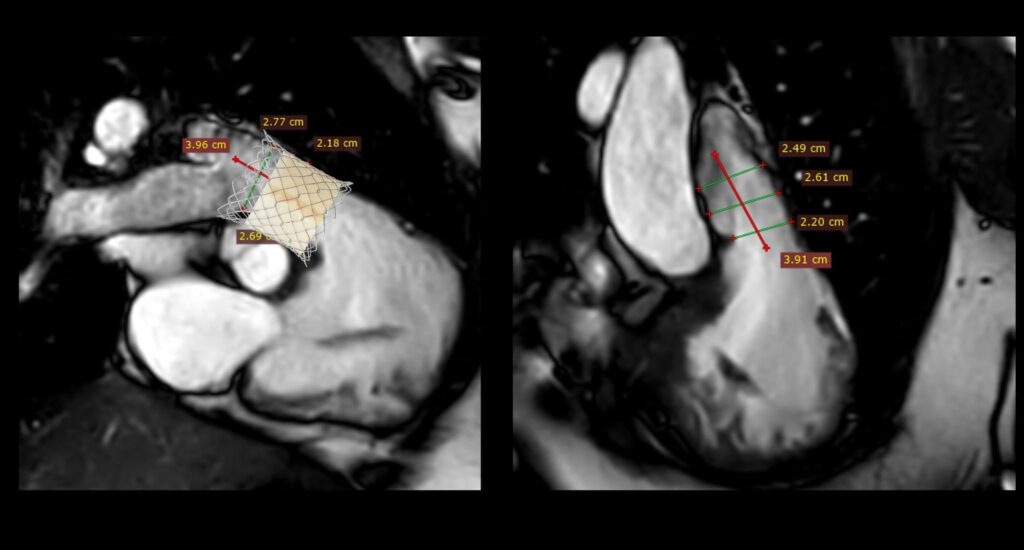

คณะแพทยศาสตร์ มช. สร้างความสำเร็จทางการแพทย์ ด้วยการรักษาโรคลิ้นหัวใจพัลโมนิกรั่ว (Pulmonary valve regurgitation) ผ่านสายสวน ในผู้ป่วยหญิงไทย อายุ 22 ปี ที่มีประวัติผ่าตัดรักษาภาวะ Tetralogy of Fallot มาก่อน และมีอาการของลิ้นพัลโมนิกรั่วรุนแรง

การใส่ลิ้นหัวใจพัลโมนิกเทียมผ่านสายสวนหัวใจ (Transcatheter pulmonary valve implantation; TPRI ) ในครั้งนี้ ทำผ่านทางหลอดเลือดดำใหญ่ บริเวณขาหนีบ จึงไม่ต้องผ่าตัดเปิดทรวงอก โดยกระบวนการรักษาและพักฟื้นผ่านไปได้ด้วยดี ไม่พบภาวะแทรกซ้อน ผู้ป่วยสามารถออกจากโรงพยาบาล 2 วันภายหลังการรักษา นับเป็นหนึ่งในความก้าวหน้าของนวัตกรรมการแพทย์เพื่อใช้รักษา ลดความเสี่ยงของภาวะแทรกซ้อนต่างๆ รวมถึงยกระดับคุณภาพชีวิตของผู้ป่วยได้

การแก้ไขลิ้นหัวใจพัลโมนิกรั่วมี 2 วิธี คือ การผ่าตัดเปิดทรวงอกเพื่อใส่ลิ้นหัวใจพัลโมนิกเทียม และ การใส่ลิ้นพัลโมนิกผ่านทางสายสวนหัวใจ การเปลี่ยนลิ้นทั้งสองวิธีนี้เมื่อเวลาผ่านไป 10-20 ปี ลิ้นพัลโมนิกเทียมจะมีโอกาสเสื่อมอีก ทำให้ผู้ป่วยประมาณ 1 ใน 3 จำเป็นต้องเปลี่ยนลิ้นหัวใจซ้ำอีกครั้ง ซึ่งในผู้ป่วยบางรายอาจจะต้องการการใส่ลิ้นพัลโมนิกเทียมไม่ว่าจะโดยการผ่าตัดหรือผ่านทางสายสวน 2-3 ครั้งในช่วงชีวิตหนึ่ง

การผ่าตัดเปิดทรวงอกในแต่ละครั้ง จะก่อให้เกิดพังผืด (fibrous adhesion) เพิ่มความยากลำบาก และความเสี่ยงในการผ่าตัดมากขึ้น การรักษาผ่านทางสายสวนจึงเป็นทางเลือกที่จะลดความเสี่ยงนี้ลง อีกทั้งยังสามารถใส่ลิ้นพัลโมนิกเทียมชิ้นใหม่ทับแทนชิ้นเก่าได้ (valve in valve procedure)